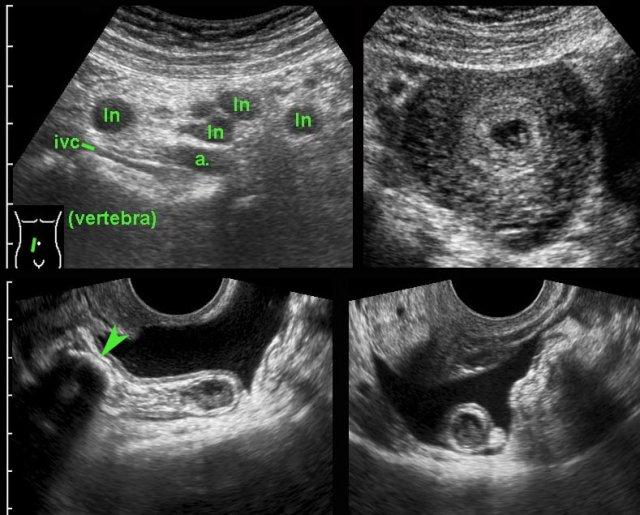

Viêm ruột thừa

Bệnh nhân nữ trẻ, mang thai giai đoạn sớm, nhập viện vì đau vùng chậu sâu cấp tính.

Siêu âm phát hiện các hạch bạch huyết mạc treo phì đại (ln) và thai trong buồng tử cung còn nguyên vẹn.

Ruột thừa không được hiển thị. (ivc = tĩnh mạch chủ dưới, a = động mạch chậu).

TVUS dễ dàng phát hiện ruột thừa viêm đường kính 12 mm chứa sỏi phân lớn (đầu mũi tên).

Ruột thừa nằm ở vị trí trong vùng chậu và được bao quanh bởi dịch tự do.

Không có thủng tại thời điểm phẫu thuật.

Ở bệnh nhân nữ béo phì, mang thai 3 tuần này, siêu âm qua thành bụng chỉ hiển thị được ruột thừa với hình ảnh nghi ngờ bất thường (← ?).

TVUS cho thấy ruột thừa giãn to, chứa đầy mủ, đang trong tình trạng viêm, nằm ở vị trí sâu trong vùng chậu.